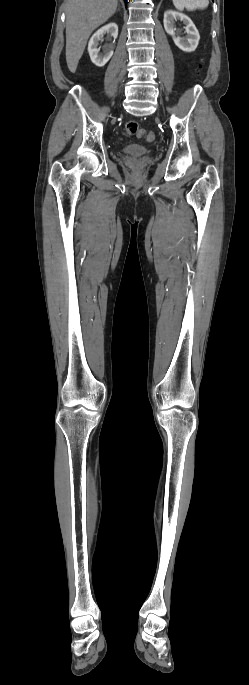

Назад КТ брюшного отдела аорты и сосудов (артерий) нижних конечностей

КТ брюшного отдела аорты и сосудов (артерий) нижних конечностей

13 500 руб